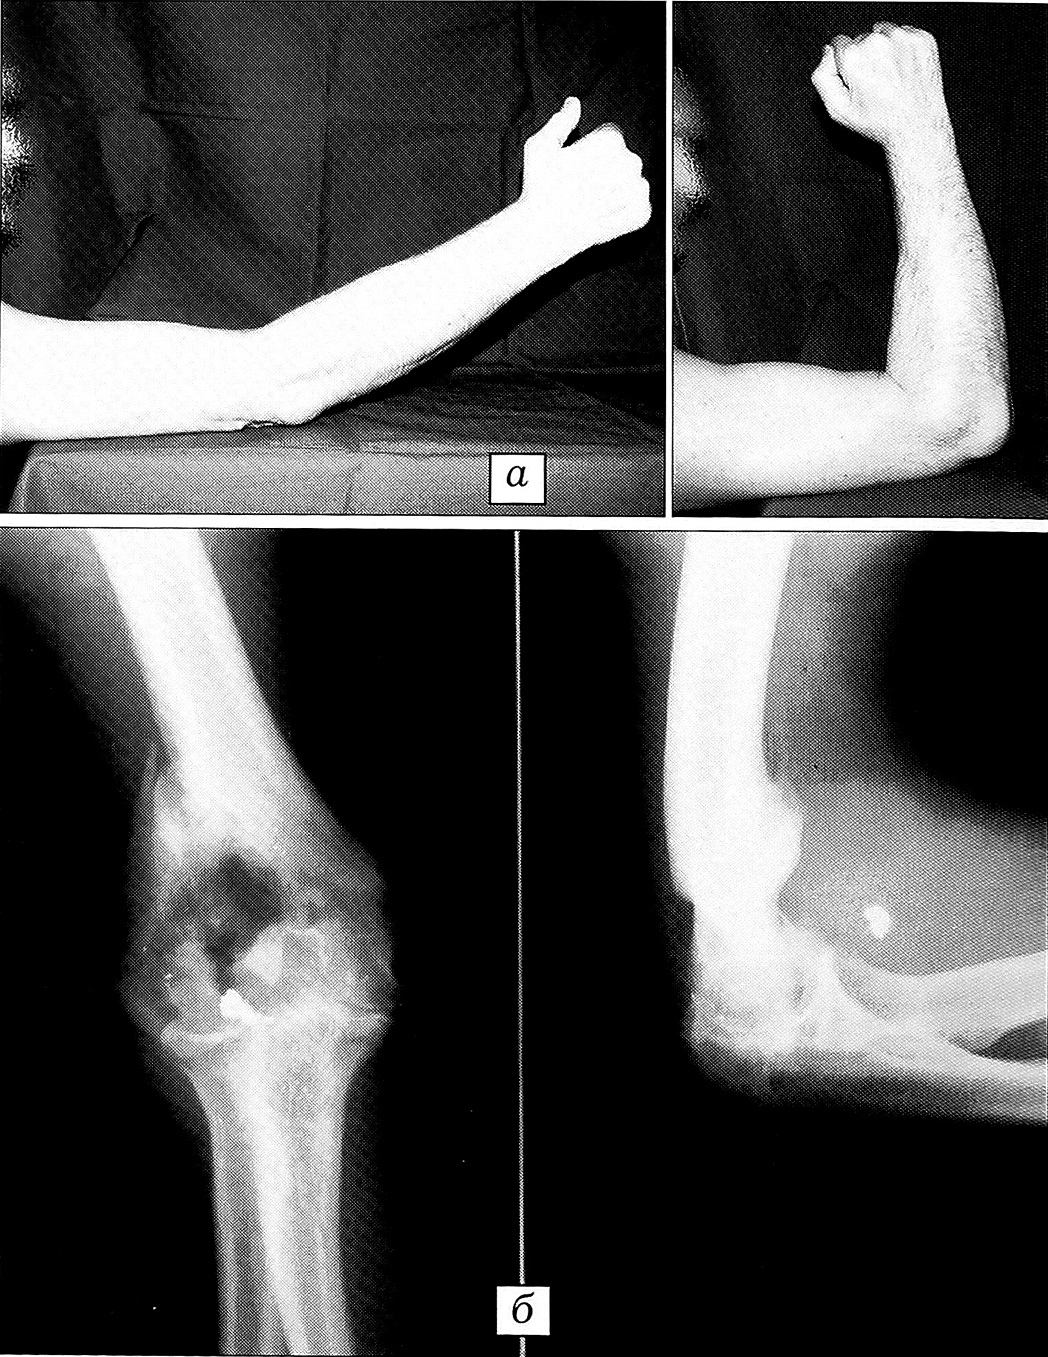

Больной К., 42 лет. Клинический диагноз: огнестрельный ложный сустав дистального эпиметафиза правой плечевой кости; повреждение локтевого нерва. Огнестрельное (минно-взрывное) ранение локтевого сустава получил во время боевых действий. Попытки репозиции, неоднократно предпринимавшиеся после заживления раны, оказались безуспешными. Через 7,5 мес больной обратился в нашу клинику с жалобами на существенное ограничение движений в правом локтевом суставе, затрудняющее профессиональную и бытовую деятельность. При поступлении выявлены гипотрофия возвышения V пальца кисти, уменьшение ширины ладони за счет сближения межпястных промежутков, парестезии в зоне иннервации локтевого нерва. Движения в локтевом суставе ограничены: сгибание — 90°, разгибание — 155°, пронация и супинация в пределах 5° (рис. 1, а).

На рентгенограммах правого локтевого сустава: угол между плечевой костью и костями предплечья 165°, щель сустава резко сужена, плечелучевой сустав не определяется. Наружный надмыщелок 2x5,5 см, клиновидной формы с острой проксимальной верхушкой, смещен латерально, ротирован кнутри и наклонен кпереди вершиной под углом 30°. Диастаз между фрагментом головочки надмыщелка и большей ее частью 4 мм. Плечелоктевой сустав резко сужен, контурируется (рис. 1, б).

Рис. 1. Больной К. 42 лет. Огнестрельный ложный сустав дистального эпиметафиза правой плечевой кости; повреждение локтевого нерва. При поступлении.а — разгибание, сгибание в локтевом суставе; б — рентгенограммы локтевого сустава.